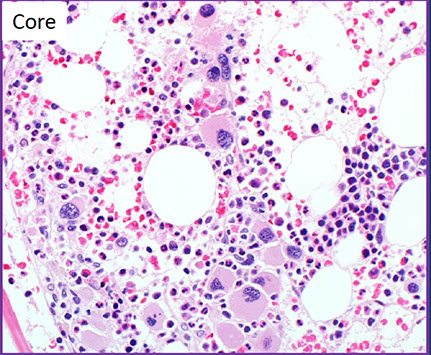

Low power morphologic abnormalities in MDS

- hypercellular marrow (80% of cases)

BM findings

Usually hypercellular marrow for age with erythroid hyperplasia, but may see normocellular or hypocellular marrow

Generally increased number of blasts

Generally trilineage dysplasia (dyshematopoiesis)

- Abnormal localization of immature myeloid precursors (ALIP)